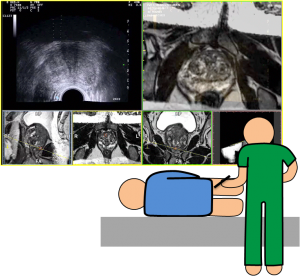

Biópsia prostática orientada por fusão de imagem (RM-US)

A técnica de biópsia mais frequentemente realizada e aceita como atual método de referência é a biópsia prostática randômica em duplo sextante guiada por ultrassonografia transretal.

Por outro lado a  ressonância magnética (RM) apresenta elevada resolução espacial e de contraste tecidular, permitindo uma melhor visualização da próstata e de alterações patológicas da mesma, em comparação com a ecografia prostática transretal.

A capacidade de detetar e delinear lesões fortemente sugestivas de tumor nas imagens de RM levou ao desenvolvimento de novas técnicas de biópsia prostática dirigidas: biópsia guiada por fusão entre as imagens da RM e imagens em tempo real obtidas por ecografia prostática transretal (US).

A técnica de fusão cognitiva envolve a visualização prévia das imagens de RM com identificação das lesões suspeitas, tentando‐se, posteriormente, através de ecografia transretal, estimar o local onde se encontrarão essas lesões e biopsá‐las. Para melhor localizar as lesões deve recorrer‐se a pontos de referência anatómicos que possam ser visíveis na RM e na ecografia.

Desta forma a fusão de imagens de RM com USG para biópsia de próstata, para a orientação de lesões suspeitas resultará em biópsias mais precisas e diminuirá o número de procedimentos necessários para a detecção de doença clinicamente significativa.